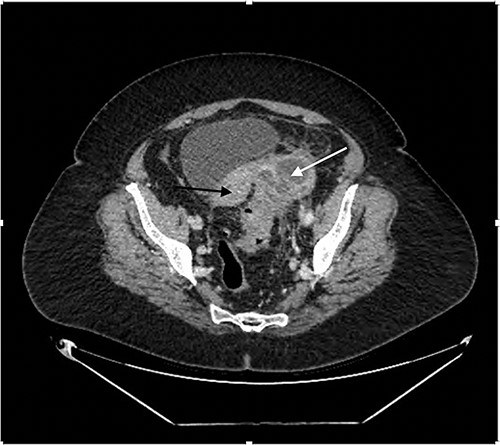

In 4 months, following an exacerbation of LIF pain, outpatient CT demonstrated the LIF mass had now progressed in size, up to 9.0 × 7.0 × 5.3 cm in dimension, with now multiple air fluid levels, accompanied with complete loss of the tissue planes between the lesion and the sigmoid colon. There was also free fluid in the Pouch of Douglas (POD), as seen in Fig. 3. As such, the conclusion was made that the patient had likely chronic Hinchey Class 2 diverticular abscess, requiring operative intervention.

Contrast enhanced coronal CT Abdomen/Pelvis revealing a larger multi-loculated rim enhancing LIF mass (white arrow) adherent to the uterus (black arrow), with air fluid levels and multiple locules of gas.